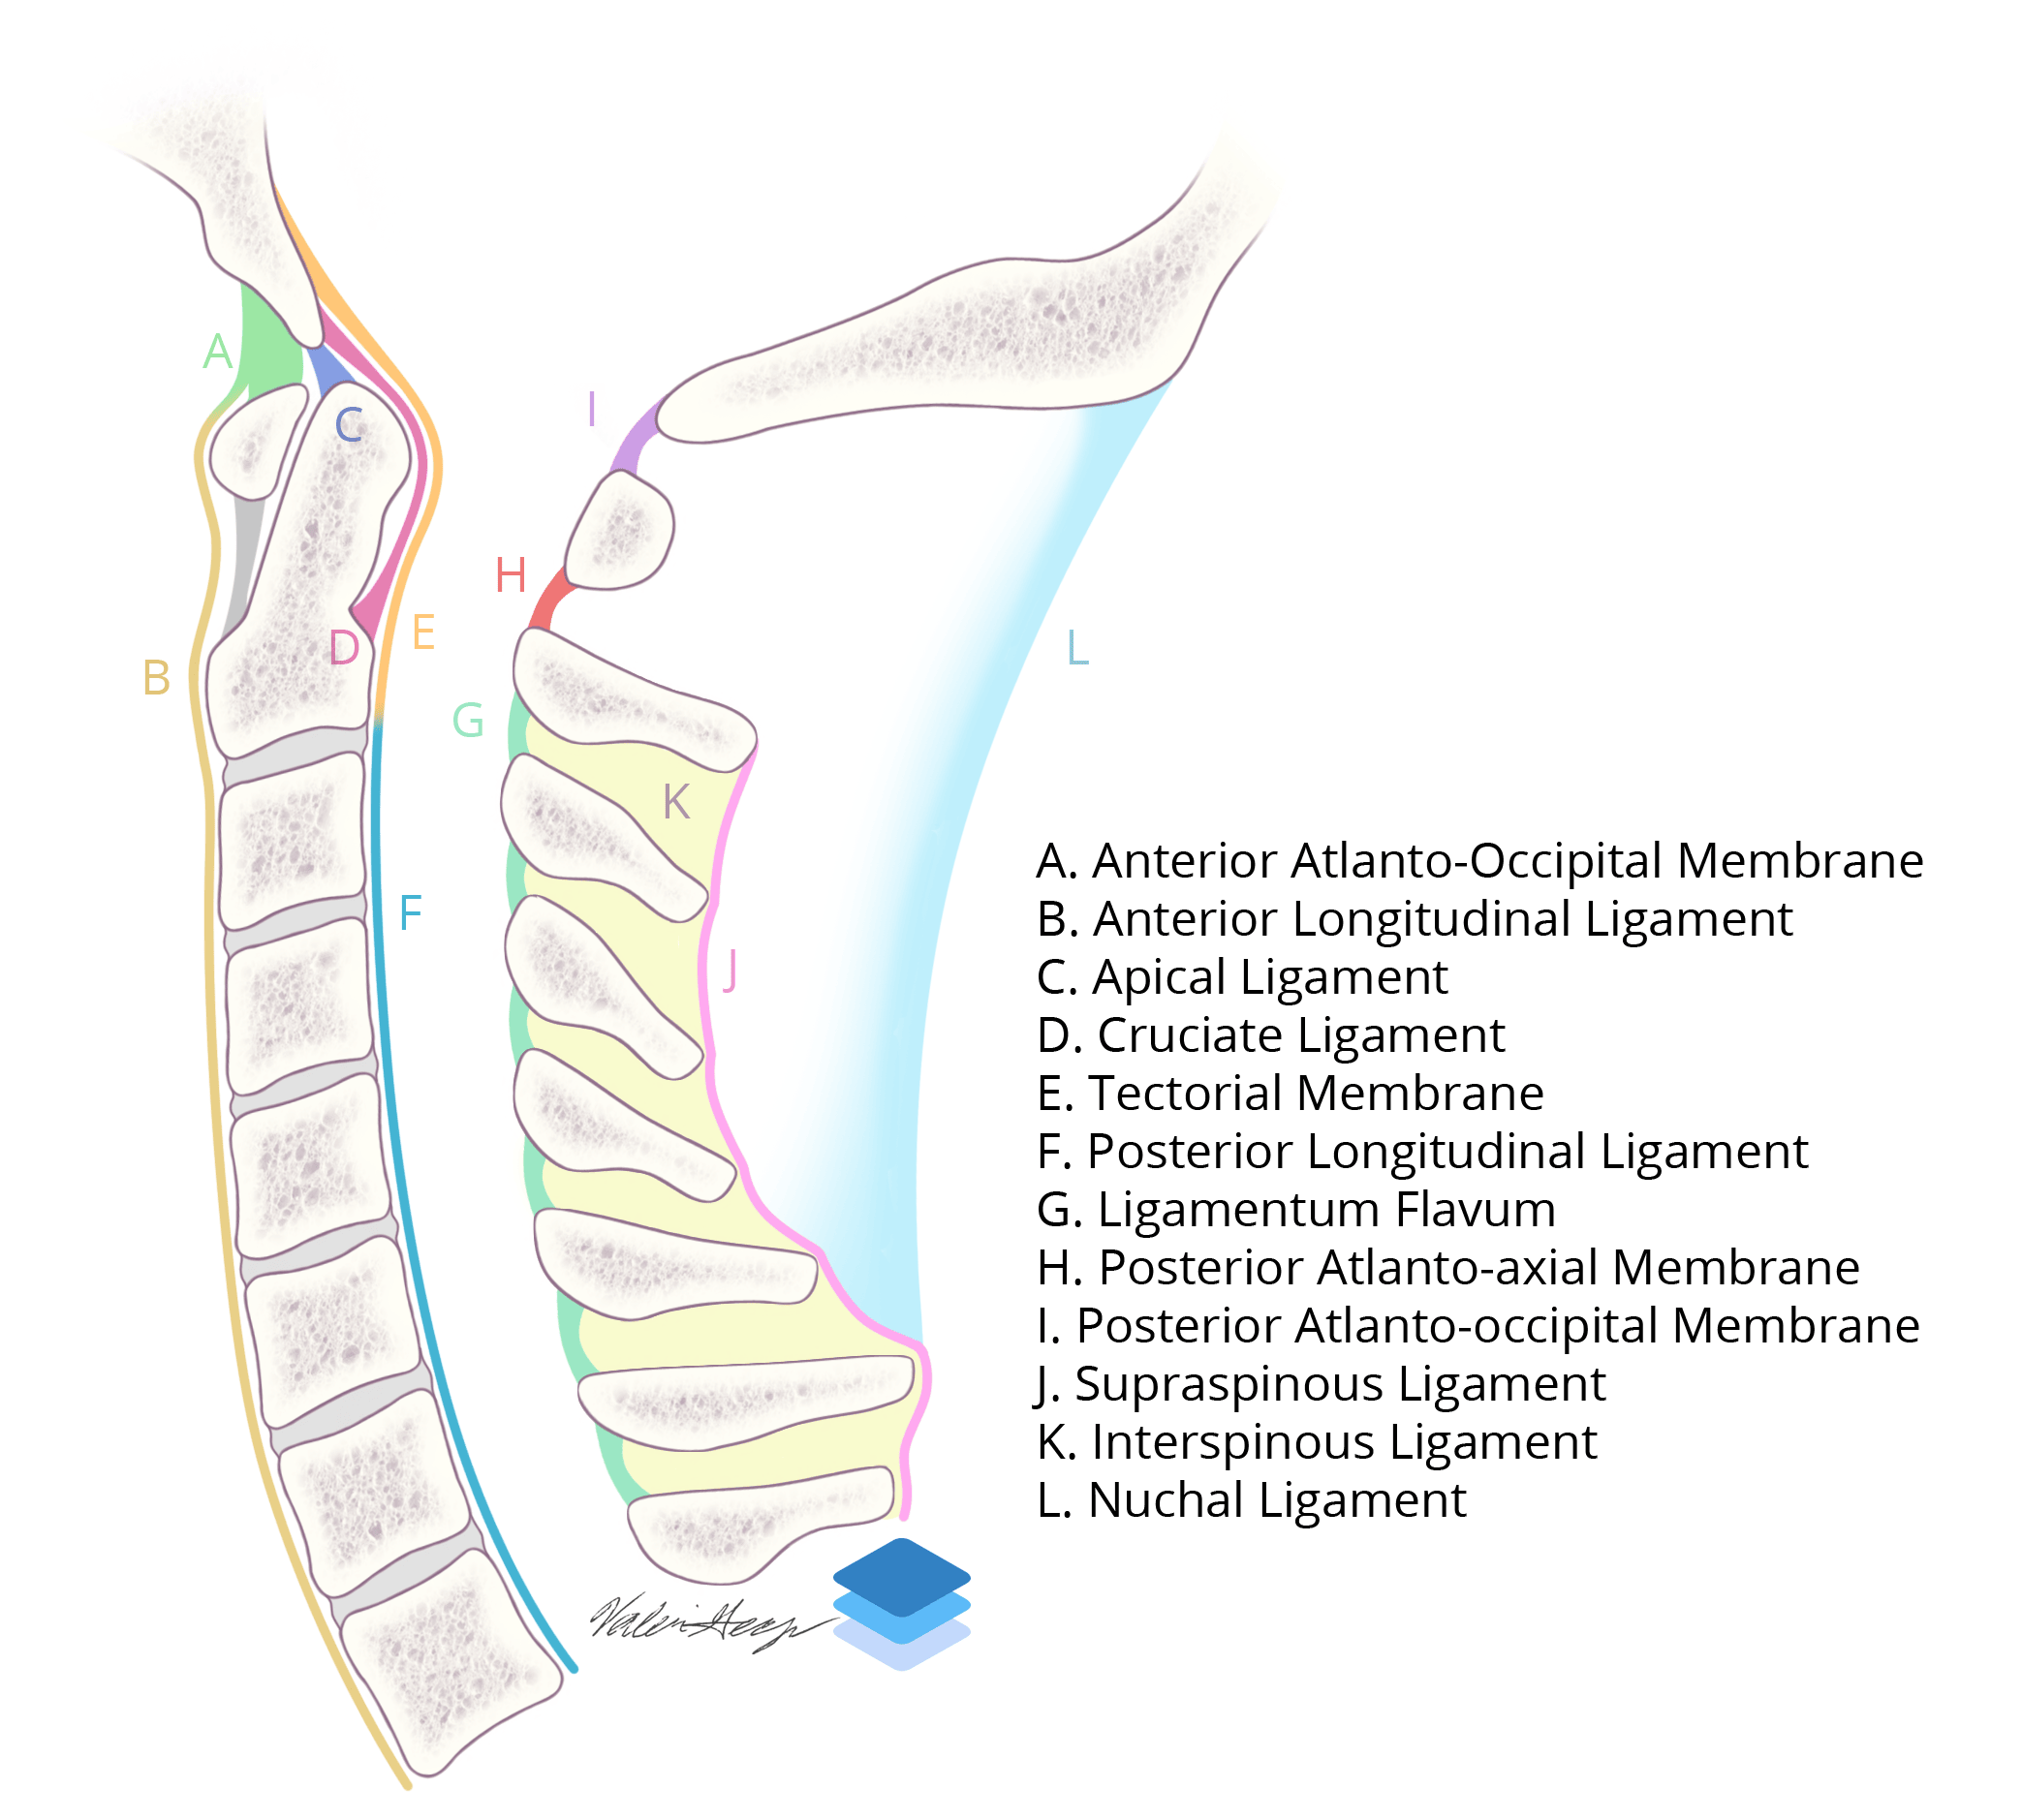

- Below the craniocervical junction (i.e. below the level of C2), the important ligaments to assess are the:

- Anterior longitudinal ligament

- Posterior longitudinal ligament

- Ligamentum flavum

- Interspinous ligaments

- Supraspinous ligament

Sagittal Cervical Spine Ligaments